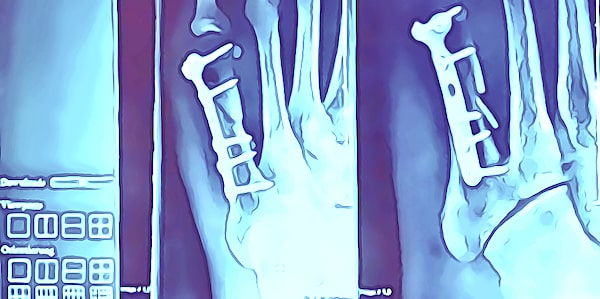

. - Geeignete Untersuchungsmethoden auswählen.

Röntgenaufnahmen eignen sich zur Bestimmung von Frakturen, sowie von von altersbedingten Veränderungen (z.B. Osteoporose). Kernspintomografie / Magnetresonanztomografie (MRT) eignen sich zur Feststellung von Verletzungen insbesondere an Weichteilen.